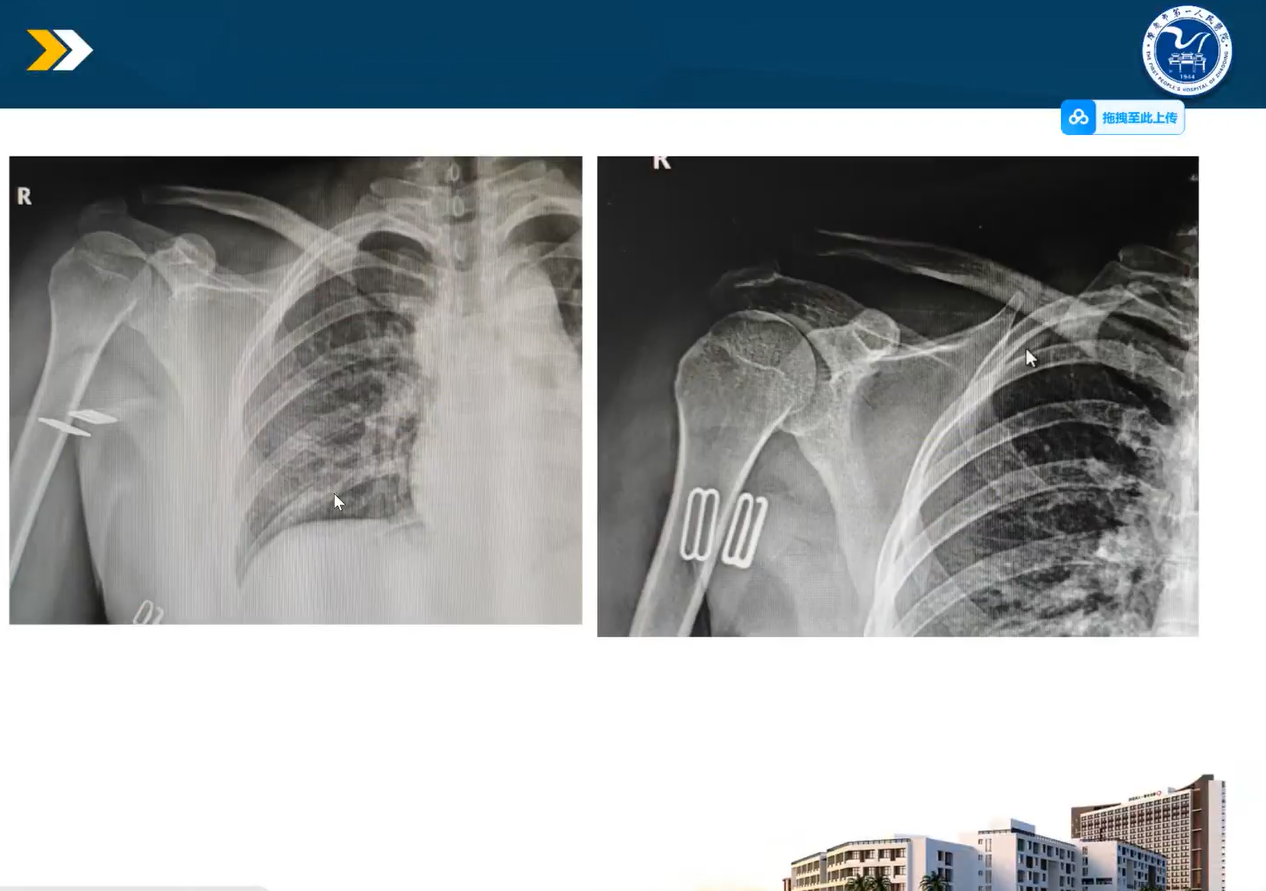

▲ 肇庆市第一人民医院关节科主任林宇宁,分享关于“肩锁关节脱位全缝线处理”的治疗方法,通过实际临床病例为大家讲解及分析。

▲ 林主任从流行病学、解剖学、生物力学、损伤分型、治疗方式等维度对肩锁关节脱位进行了阐述,详细介绍了锁骨钩钢板到带袢钛板再到全缝线锚钉等不同耗材应用于肩锁脱位的治疗。在病例分享中对弹性固定和全缝线锚钉的实际应用进行了充分交流。

▲ 十堰市人民医院杨威,分享关于“关节镜下缝线锚钉复位固定肩胛孟骨折”,通过文献复习及实际临床病例为大家讲解及分析。

▲ 杨主任从肩胛盂骨折的概述、分型、诊断及治疗等方面进行了讲解,分享了切开治疗和镜下治疗肩胛盂骨折的对比,详细介绍了缝线锚钉如何在镜下治疗肩胛盂骨折。